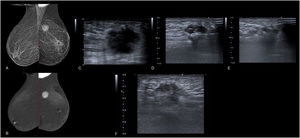

A) Imagen de RM. Secuencia dinámica T1 con saturación grasa y administración de gadolinio IV. Nódulo de morfología y bordes irregulares en el cuadrante inferointerno de la mama izquierda con captación de contraste heterogéneo (curva tipo 3). Está localizado a 17 mm de la piel, 56 mm del complejo aréola-pezón y 96 mm de la pared torácica. Tras la realización de BAG, se obtuvo un resultado de carcinoma ductal infiltrante Luminal A. B-D) Imágenes de la ablación guiada por ecografía. B) Nódulo hipoecoico de morfología irregular y bordes espiculados. Se planifica el abordaje desde los cuadrantes internos. C) Se atraviesa el eje longitudinal del tumor y el bisel de la sonda sobrepasa la lesión. D) Durante el procedimiento se van evidenciando cambios en la estructura tumoral, con desarrollo de una hiperecogenicidad progresiva. E) Imagen ecográfica del control realizado al mes de la intervención, donde se observa la formación de un área de necrosis grasa.

Tras aplicar las medidas antisépticas adecuadas, se administra anestesia local, en nuestro caso bupivacaína 2,5 mg/ml y lidocaína 20 mg/ml, haciendo hincapié en una infiltración precisa de todos los bordes de la lesión. Posteriormente se procede a introducir la antena de microondas siguiendo el eje longitudinal de la lesión y centrando la aguja en la mitad del tumor, quedando el bisel sobrepasando ligeramente la parte distal (5 mm) de manera que la punta activa quede normoposicionada, teniendo en cuenta que la ablación se realiza desde el bisel hacia atrás (fig. 1). Tras comprobar el correcto posicionamiento de la sonda, se aplica la potencia seleccionada durante el tiempo requerido, pudiendo ser necesario dividir el procedimiento en 2 pases en función del tamaño y la morfología de la lesión, ya que el sistema permite realizar ablaciones de forma ovoide (fig. 2). Finalmente, se procede a ejecutar el tracking de salida, que consiste en tratar con ablación el tracto de salida de la aguja para minimizar la siembra tumoral en el trayecto.

Durante el procedimiento, desde el momento en que comienza a aplicarse la potencia oportuna, comenzaremos a ver áreas hiperecogénicas en la zona de ablación, que van confluyendo hasta que la lesión a tratar se vuelve completamente hiperecogénica, lo que indicaría éxito del procedimiento.

Entre los hallazgos radiológicos evidenciados en el seguimiento posintervención se observó el desarrollo progresivo de un área de necrosis grasa, inicialmente con degeneración quística interna, la cual ofrecía una imagen de aumento de tamaño de la lesión en la ecografía del primer mes, de características marcadamente hipoecoicas (figs. 1 y 4).